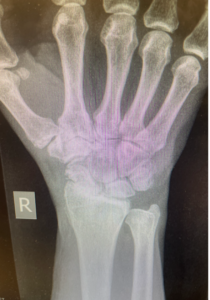

A thorough diagnosis begins with a physical examination and imaging studies.

- The surgeon will assess range of motion, swelling, and alignment of the carpal bones.

- X-rays of the wrist bones show narrowing of joint spaces, bone spurs, or irregular joint surfaces.

- Blood tests can help identify inflammatory arthritis such as rheumatoid arthritis or psoriatic arthritis caused by autoimmune disease.

This information helps develop a proper treatment plan tailored to the severity of arthritis symptoms and wrist motion limitations.